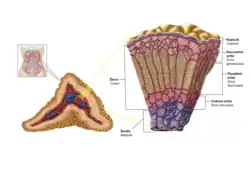

| Adrenal Glands Zonations | |

| Adrenal Glands Zonations | |

Study of the reported cases indicate that most adrenocortical adenomas occur due to neoplastic proliferation of adrenal cortical cells within the three distinct layers of adrenal cortex. In humans, the adrenal cortex comprises three concentric zones including the zona glomerulosa, zona fasciculata, and zona reticularis that under normal conditions respond to body's physiological demands for steroid hormones. The adrenal cortex is considered a dynamic organ in which senescent cells are replaced by newly differentiated cells. This constant renewal facilitates organ remodeling which contributes to dynamic characteristics of the adrenal cortex. [7] correspondingly, the developmental physiology of the adrenal cortex is believed to play a pivotal role in formation of the adrenocortical tumors. Hence, the molecular mechanisms involved in normal development of the adrenal glands are like double edged swords that can lead to the formation of tumors within the adrenal cortex. Moreover, recent studies suggest that mutations affecting the molecular pathways of the adrenocortical region can stimulate abnormal proliferation and tumor formation. Through these studies, the cyclic AMP-dependent protein kinase A signaling has been identified as a key mediator of cortisol secretion, and the mutations associated with the dysregulation of cyclic AMP - protein kinase A pathways have been implicated in the adrenocortical pathophysiology.[8]

If functional, adrenocortical adenomas can affect the normal activities of the adrenal cortex. Located within the adrenal glands are the three zones that are responsible for secretion of the three major classes of adrenal steroids. Hence, functional adrenocortical adenomas can induce over-secretion of adrenal steroids associated with pure or mixed endocrine syndromes, a condition commonly known as hyperadrenalism.